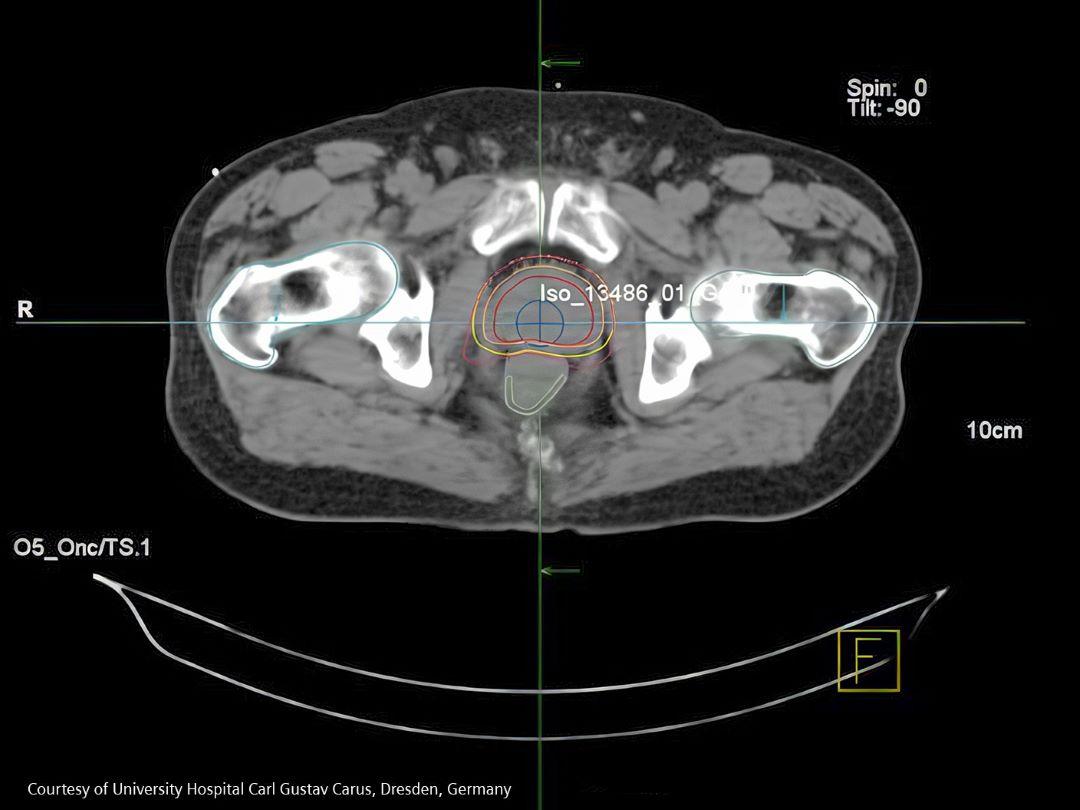

Treatment

Catching prostate cancer early makes it highly curable.

VARIAN EclipseTM IMRT (Intensity Modulated Radiotherapy) plan for a prostate cancer patient.1